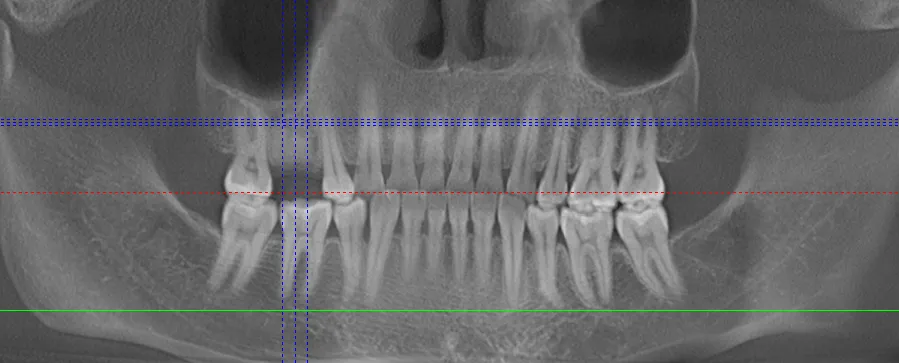

口腔检查:口腔专科检查必不可少。医生会通过口腔X光片、CT等影像检查,精确评估牙槽骨的质量、密度、高度及宽度等情况,以此判断是否适合种植。若牙槽骨骨量不足,可能需要先进行骨增量手术,如骨粉植入,为种植体提供稳固的基础。同时,还会检查口腔卫生状况,若存在牙周炎等问题,需先治疗,确保口腔处于健康状态。

种植手术过程

植入种植体:医生会在牙槽骨上制备一个合适的种植窝,然后将种植体精确植入其中。这一过程需要医生具备丰富的经验和精湛的技术,以保证种植体的位置、角度和深度符合要求。种植体就如同人工牙根,植入后会与牙槽骨紧密结合,为后期的牙冠修复提供稳定支撑。